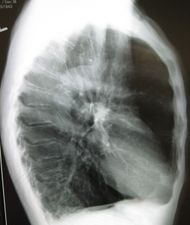

A lateral chest x-ray of a person with emphysema. Note the barrel chest and flat diaphragm. | |